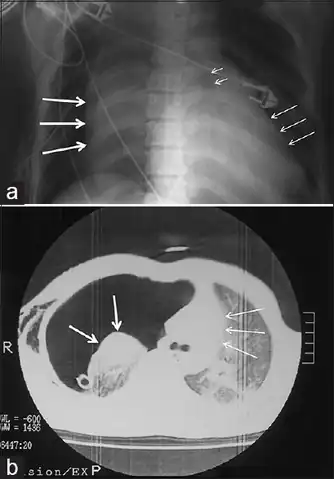

a)Collapsed right lung , left deviated trachea , and shifted heart b) chest illustrating collapsed right lung and shifted heart -

Chest x-ray is the initial imaging technique used to diagnose TBI.[17] The film may not have any signs in an otherwise asymptomatic patient.[15] Indications of TBI seen on radiographs include deformity in the trachea or a defect in the tracheal wall.[17] Radiography may also show cervical emphysema, air in the tissues of the neck.[2] X-rays may also show accompanying injuries and signs such as fractures and subcutaneous emphysema.[2] If subcutaneous emphysema occurs and the hyoid bone appears in an X-ray to be sitting unusually high in the throat, it may be an indication that the trachea has been severed.[4] TBI is also suspected if an endotracheal tube appears in an X-ray to be out of place, or if its cuff appears to be more full than normal or to protrude through a tear in the airway.[17] If a bronchus is torn all the way around, the lung may collapse outward toward the chest wall (rather than inward, as it usually does in pneumothorax) because it loses the attachment to the bronchus which normally holds it toward the center.[6] In a person lying face-up, the lung collapses toward the diaphragm and the back.[23] This sign, described in 1969, is called fallen lung sign and is pathognomonic of TBI (that is, it is diagnostic for TBI because it does not occur in other conditions); however it occurs only rarely.[6] In as many as one in five cases, people with blunt trauma and TBI have no signs of the injury on chest X-ray.[23] CT scanning detects over 90% of TBI resulting from blunt trauma,[3] but neither X-ray nor CT are a replacement for bronchoscopy.[6]